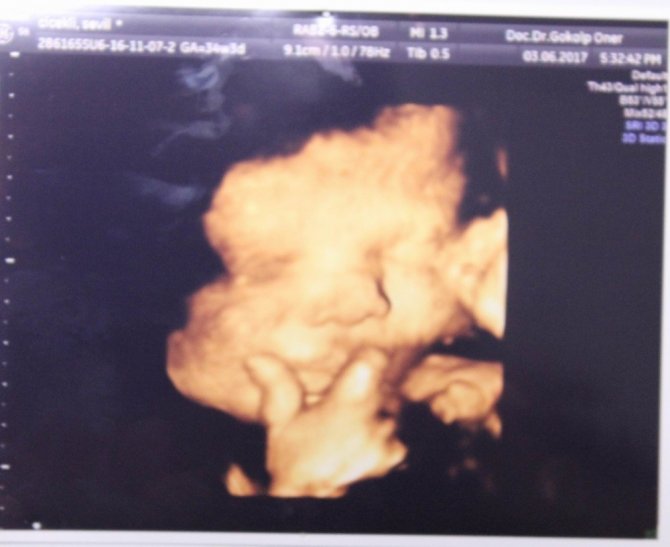

Anne karnındaki bebeklerin çekildiği dört boyutlu ultrason fotoğraflara takılan pozlar bazen şaşırtıyor. Henüz 22 haftalıkken zafer işareti yapan bebeğin fotoğrafı bunlardan en ilgi çekici olanı.

Memorial Kayseri Hastanesi Kadın Hastalıkları ve Doğum Uzmanı Doç. Dr. Gökalp Öner'in yaklaşık 2 yıldır çektiği 400'ün üzerinde, dört boyutlu ultrason fotoğraflara takılan anne karnındaki bebeklerin ilginç pozları dikkat çekiyor. Zafer işareti yapan, burnunu karıştıran, dilini çıkaran, uzun hava çeken, düşünen bebek fotoğrafları ebeveynleri hem mutlu ediyor hem de şaşkınlığa uğratıyor.

Anne karnındaki fotoğrafları 22'nci haftadan itibaren aldıklarını söyleyen Doç. Dr. Gökalp Öner, "Dört boyutlu olarak anne karnındaki bebeklerimizin yüzünü, ellerini, ayaklarını görüntüleyebiliyoruz. Bunlar aileye mutluluk veriyor. Anne ve babanın bebeğin iyi olduğunu, nasıl olduğunu görmelerini sağlıyor hem de bağlılık duygusunu sağlıyor. Anne adaylarının bebeği canlı canlı görmesi bebeklerine bağlanmasını daha çok artırıyor. Bebekleri ile çok bağ kuramayan babalar, çocuklarını gördükleri zaman daha çok bağlanıyorlar. Onların güvende olduklarını gördüklerinde de rahatlıyorlar ve mutluluk duyuyorlar. Bu dört boyutlu ultrason resimlerimiz, hem bize hem aileye mutluluk ve güven veriyor" diye konuştu.

Mutlu geçirilmesi gereken hamilelik dönemini bu fotoğraflarla renklendirdiklerini dile getiren Doç. Dr. Gökalp Öner, "Bu fotoğraflarda bazen ilginç pozlar yakalıyoruz. Bebeklerimiz ağlarken, gülerken, düşünürken, zafer işareti yaparken, burnunu karıştırırken... Bunları yakaladığımızda ailenin de bizim de hoşumuza gidiyor. Böyle mutlu anları paylaşıyoruz. Çünkü gebelik süreci ve doğum, düğün gibi mutlu geçirilmesi gereken bir süreç" ifadelerini kullandı.